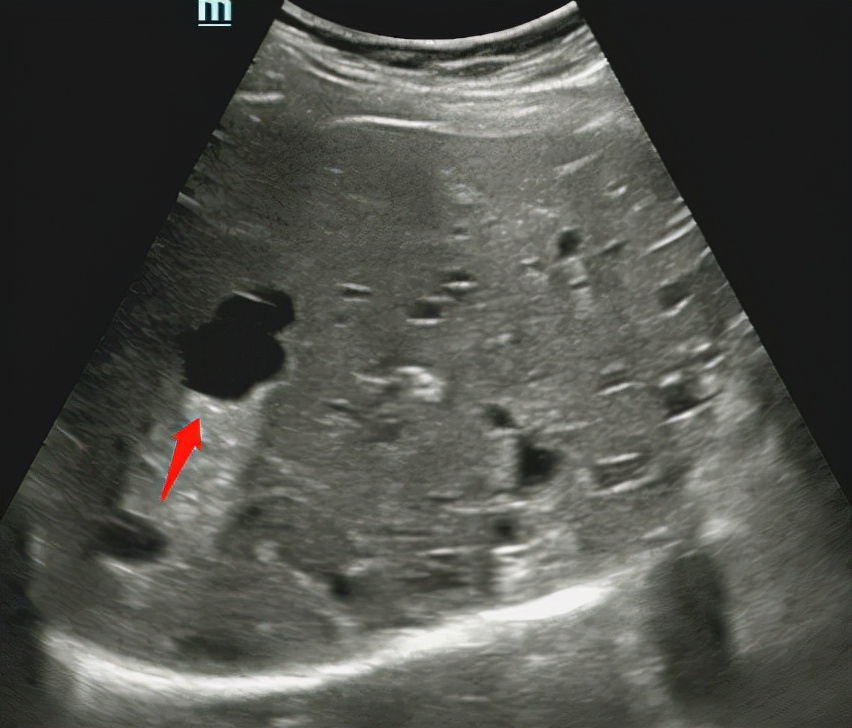

肝囊肿

肝脏较常见的良性占位有肝囊肿、肝内血管瘤。